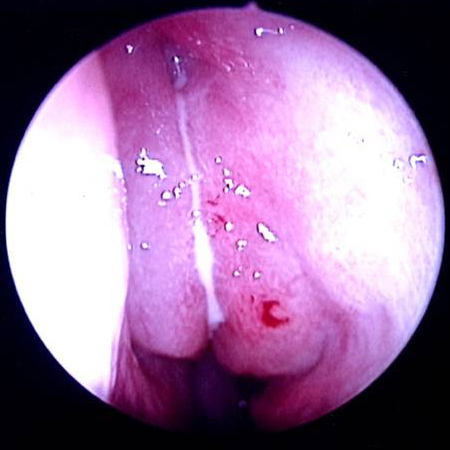

The nasal cavity should be examined for the presence of mucosal erythema or purulent discharge. Optimal exam is performed after topical decongestant spray.[18]Benninger MS, Ferguson BJ, Hadley JA, et al. Adult chronic rhinosinusitis: definitions, diagnosis, epidemiology, and pathophysiology. Otolaryngol Head Neck Surg. 2003 Sep;129(3 Suppl):S1-32. Either an otoscope or a nasal speculum and head light may be used. However, because nasal exam may be difficult or the signs nonspecific, nasal endoscopy is recommended in selected patients, including patients refractory to empiric antibiotic therapy or where there is concern for antibiotic resistance, or in immunocompromised patients.

Endoscopy can provide excellent visualization of the nasal cavity and sinus drainage paths. There are two types of endoscope: rigid and flexible. A rigid nasal endoscope has superior resolution and only requires the use of one hand. This easily allows cultures of the nasal cavity or sinus to be obtained if necessary. A flexible nasal endoscope is more comfortable for patients, but requires both hands to use. There are flexible nasal endoscopes that have a channel for collecting cultures, but these tend to be larger and more uncomfortable and they are also more difficult to reprocess. Generally, the flexible nasal endoscope is preferred in children as it is better tolerated; however, either type may be used in adults and children. Choice will depend on the practitioner's familiarity with the procedure, and most will be performed by an ear, nose, and throat specialist.

[Figure caption and citation for the preceding image starts]: Left middle meatus with severe edema and purulent secretionsFrom the collection of Melissa Pynnonen, MD [Citation ends].

[Figure caption and citation for the preceding image starts]: Left middle meatus with healthy mucosa and non-purulent secretionsFrom the collection of Melissa Pynnonen, MD [Citation ends].

[Figure caption and citation for the preceding image starts]: Nasal endoscopy of the left nasal cavity showing a small polyp and pus in the middle meatusFrom the collection of Joseph K. Han [Citation ends].